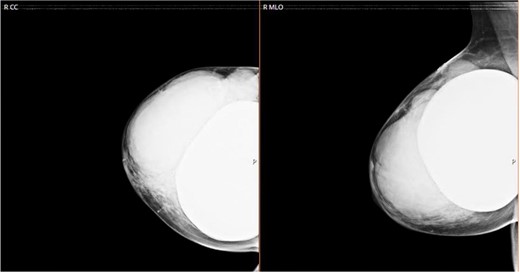

We sent for a radiological bilateral mammogram craniocaudal and mediolateral oblique, which demonstrated scattered fibro-glandular densities ACR type B in both breasts. Bilateral submammary silicone breast implants show smooth outlines with no free silicone; multiple large lobulated margin masses are replacing most of the right breast parenchyma with no associated calcification seen. The left breast appears unremarkable (Fig. 1).